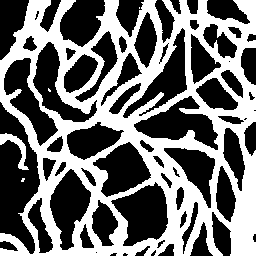

Semantic segmentation of blood vessels is an important task in medical image analysis, but its progress is often hindered by the scarcity of large annotated datasets and the poor generalization of models across different imaging modalities. A key aspect is the tendency of Convolutional Neural Networks (CNNs) to learn texture-based features, which limits their performance when applied to new domains with different visual characteristics. We hypothesize that leveraging geometric priors of vessel shapes, such as their tubular and branching nature, can lead to more robust and data-efficient models. To investigate this, we introduce VessShape, a methodology for generating large-scale 2D synthetic datasets designed to instill a shape bias in segmentation models. VessShape images contain procedurally generated tubular geometries combined with a wide variety of foreground and background textures, encouraging models to learn shape cues rather than textures. We demonstrate that a model pre-trained on VessShape images achieves strong few-shot segmentation performance on two real-world datasets from different domains, requiring only four to ten samples for fine-tuning. Furthermore, the model exhibits notable zero-shot capabilities, effectively segmenting vessels in unseen domains without any target-specific training. Our results indicate that pre-training with a strong shape bias can be an effective strategy to overcome data scarcity and improve model generalization in blood vessel segmentation.